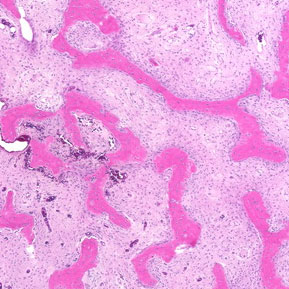

Fibrous dysplasia is a benign skeletal lesion that may present in monostotic or polyostotic forms, as well as associated with McCune-Albright syndrome. Mutation of the GNAS gene is responsible for the development of fibrous dysplasia. Pain, limp, deformity, and fractures are the main presenting symptoms. While any bone might be affected, proximal femoral involvement is the most problematic from an orthopaedic standpoint. Although medical treatment to limit the disease burden is available for the polyostotic disease, the mainstay of treatment in symptomatic cases is surgery. This current concept review is aimed at a comprehensive review of the current literature and recent developments in our understanding of fibrous dysplasia and novel treatments, with a focus on orthopaedic manifestations, particularly proximal femur deformity. We also explore the role of state-of-the-art technologies, including 3D printing, in the modern management of fibrous dysplasia.